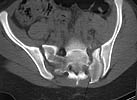

A 17 year old female involved in a car crash. Has a Type III lateral compression injury to her pelvic ring using the Young-Burgess classification. A windswept pelvis if you will. The images are included. There appears to be posterior displacement of the left hemipelvis as well.

Fx/Injury Evaluation:

Impression: unstable, requires reduction with stabilization, will continue with continued deformity if not stabilized